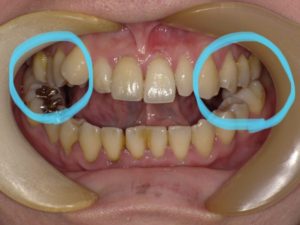

皆さんこの歯並びを見てどう思われますか?

この方は、お口を開いてる訳ではありません。

グッと噛み締めている状態になります🤣

よく見てみると奥歯だけ少し噛み合っているのが分かりますね

この歯並びは、「開咬(かいこう)」という不正咬合です。

前歯が噛み合わないため、食べ物を噛み切る事が難しくなります。